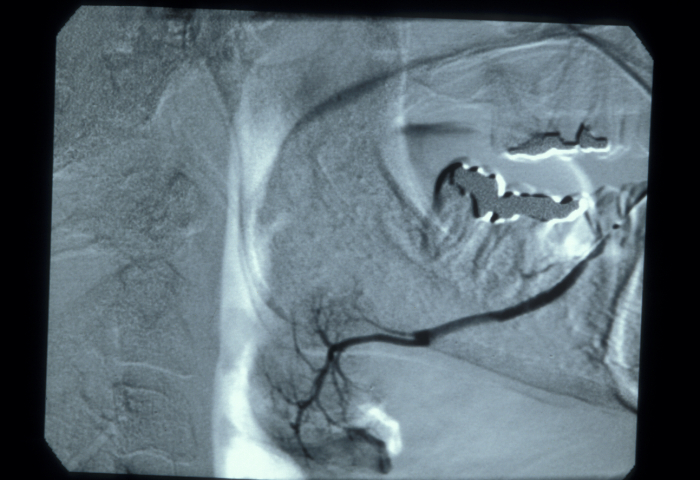

In those cases with a history of parotid swelling a sialogram will show a characteristic ‘snowstorm’ appearance of punctate sialectasis (spots of dilation of ducts) in Sjögren’s syndrome (see Figure 7). Decreased tear secretion can be measured objectively using small strips of paper placed in the lower eyelid (Schirmer’s test).

Figure 7: Sialogram showing mild ‘snowstorm’ appearance typical of sialectasis in Sjögren’s syndrome.